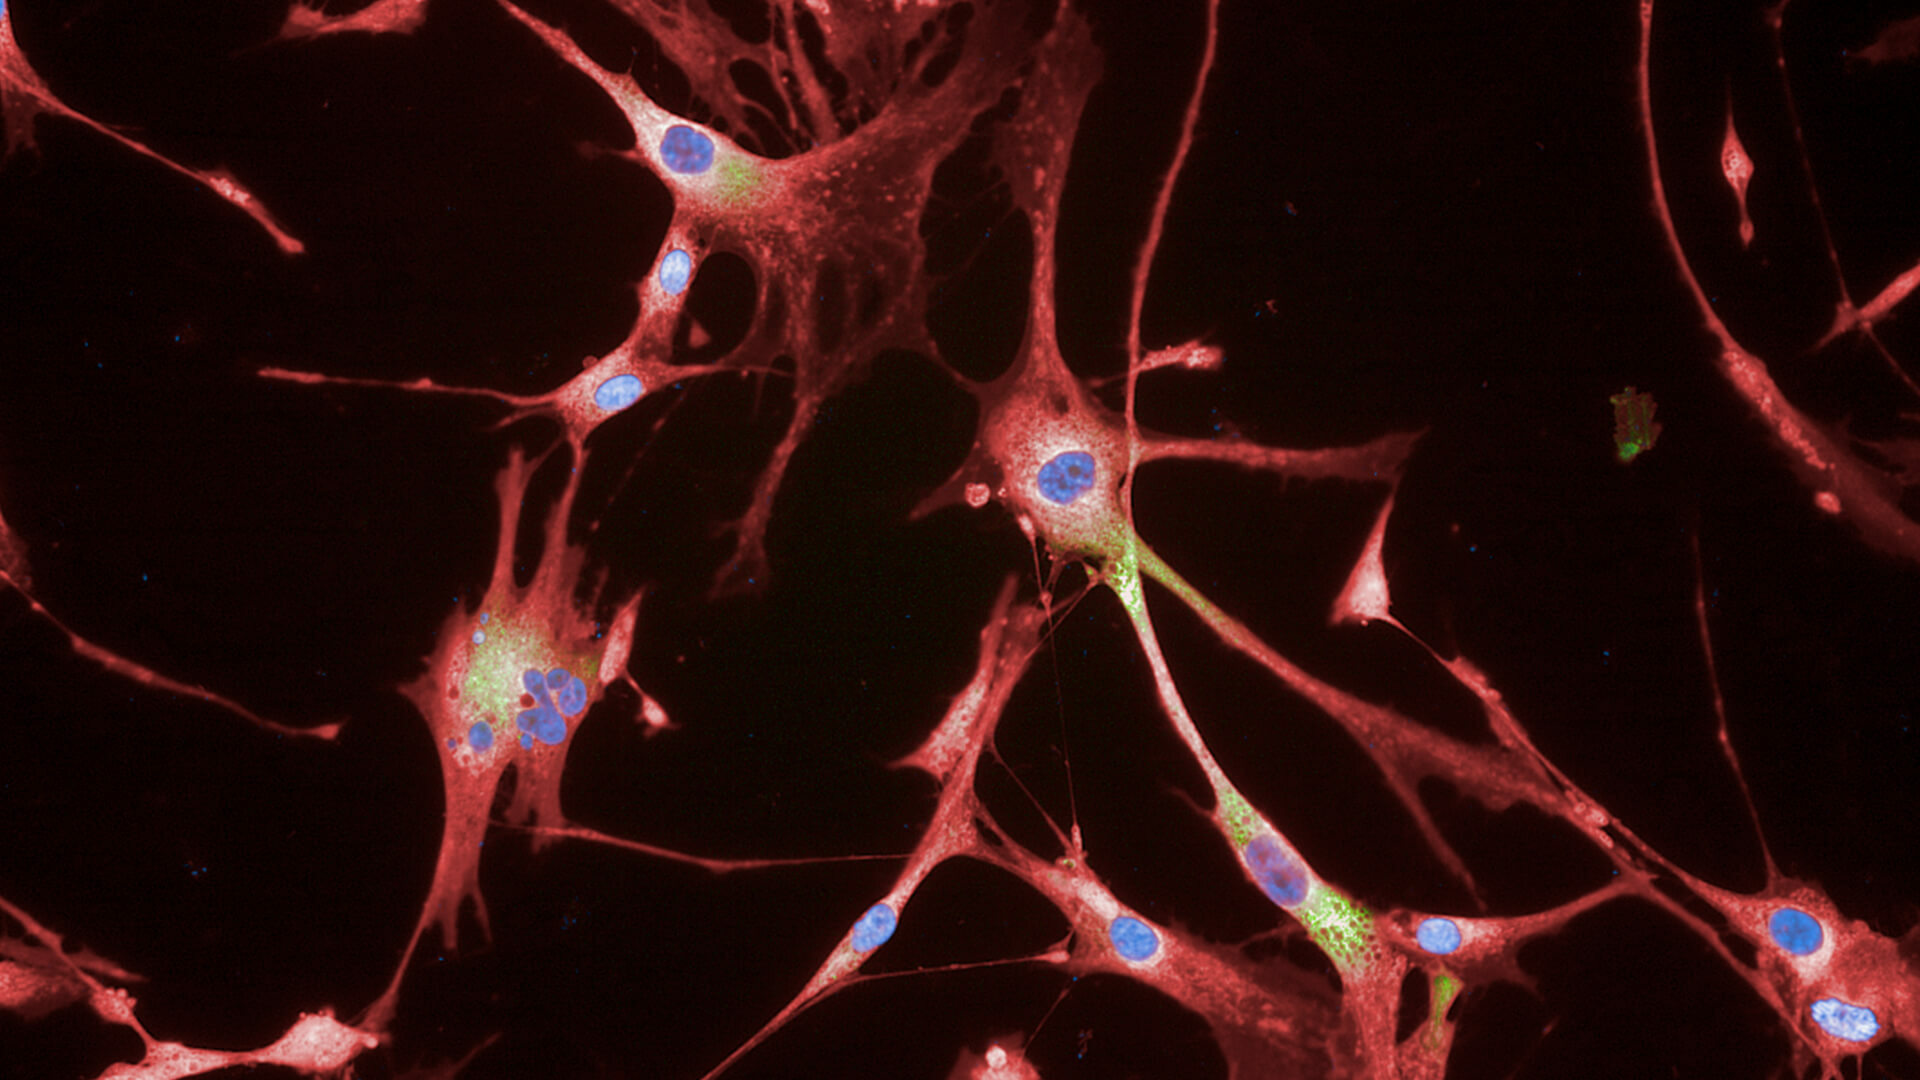

Senescent Fibroblast Cells.

Senescent Fibroblast Cells.